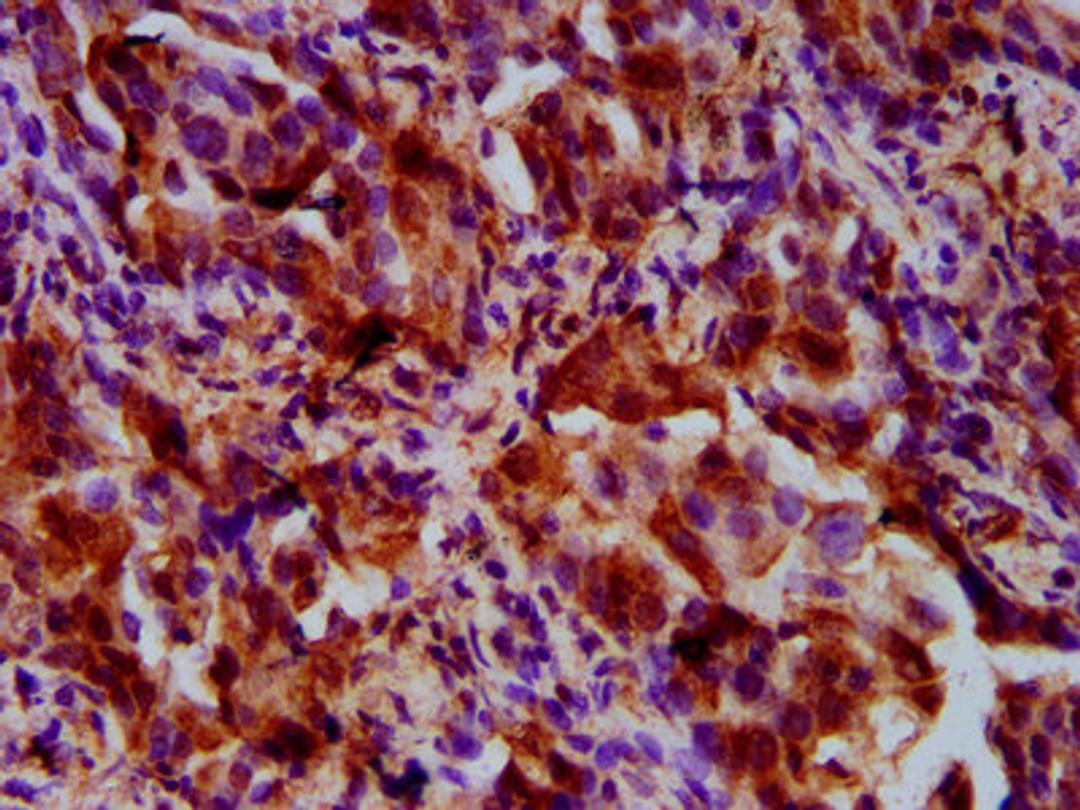

IHC image of CSB-PA883646LA01HU diluted at 1:500 and staining in paraffin-embedded human lung cancer performed on a Leica BondTM system. After dewaxing and hydration, antigen retrieval was mediated by high pressure in a citrate buffer (pH 6.0). Section was blocked with 10% normal goat serum 30min at RT. Then primary antibody (1% BSA) was incubated at 4°C overnight. The primary is detected by a biotinylated secondary antibody and visualized using an HRP conjugated SP system.